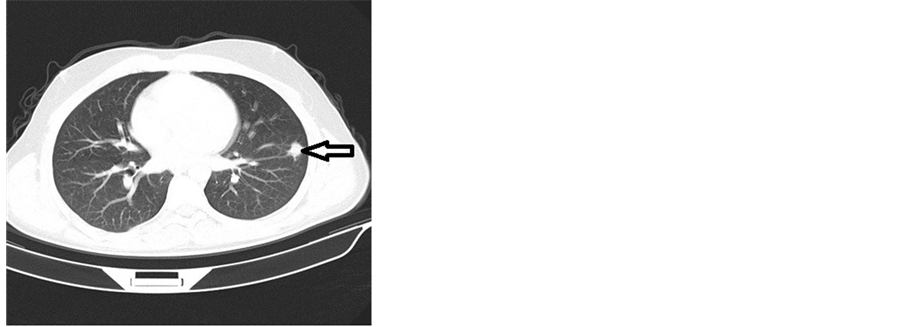

A chest CT scan revealed a tumoral process measuring 25 mm at the lower lobe of the left lung evoking a Langerhans cell histiocytosis (Figure 3).

Figure 3. Computed tomography (CT) scan of the chest showing tumoral processes at the lower lobe of the left lung.